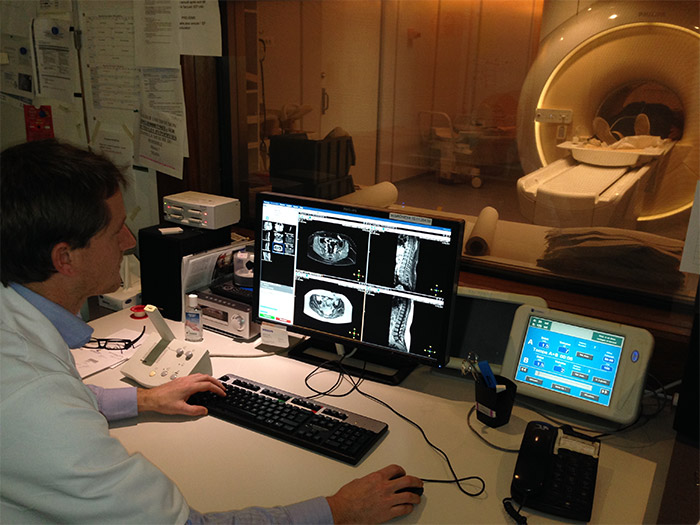

The Hospital’s musculoskeletal imaging department, led by Prof. Anne Cotten, scans patients referred from various departments including emergency, orthopedics, neurosurgery and rheumatology using its Ingenia 3.0T system. According to Guillaume Lefebvre, MD, the MRI team has recently changed its way of working by integrating mDIXON TSE into most MR exams of peripheral joints and spine. Using mDIXON TSE has contributed to detailed diagnoses and diagnostic confidence, he says.